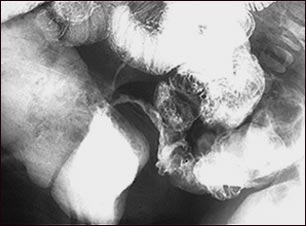

Enfermedad de Crohn; rayos X

Esta radiografía del abdomen inferior muestra un estrechamiento (estenosis) del extremo distal del intestino delgado (ileon), resultado de la enfermedad de Crohn. Esta enfermedad típicamente afecta el intestino delgado, mientras que la colitis ulcerativa afecta el intestino grueso. Esta radiografía fue tomada después de dar a beber al paciente una solución con un medio de contraste (bario), al momento en que ésta pasó por el intestino delgado (serie GI inferior).